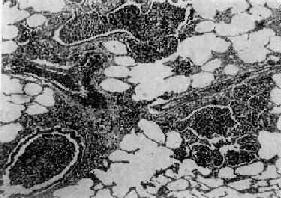

图9-15 大叶性肺炎

肺泡腔内充满纤维素性渗出物,纤维素丝穿过肺泡间孔,使相邻肺泡内的纤维素网互相连接

病变一般发生在单侧肺,多见于左肺下叶,也可同时或先后发生于两个以上肺叶。病变基本特征是肺的微循环障碍。由于毛细血管通透性增高,大量纤维蛋白原渗出于肺泡,使肺组织大面积广泛实变。病变早期,肺叶充血、水肿,肺泡腔内有大量浆液性渗出物,混有少数红细胞、中性粒细胞和巨噬细胞,并含有大量细菌。1~2天后,即有大量纤维蛋白原渗出,肺泡腔内充满混有红细胞、中性粒细胞、巨噬细胞的纤维素性渗出物,纤维素丝可穿过肺泡间孔与相邻肺泡中的纤维素网相连(图9-15)。病变肺叶质实如肝,明显肿胀,重量增加,呈灰白色(图9-16)。如血管损伤较重、出血较多,外观可呈红色。大约经5~10天,炎症消退,细菌被吞噬细胞吞噬清除,渗出物被溶解,或经淋巴管吸收或被咳出。大叶性肺炎时,肺组织常无坏死,肺泡壁结构也未遭破坏,愈复后,肺组织可完全恢复其正常结构和功能。